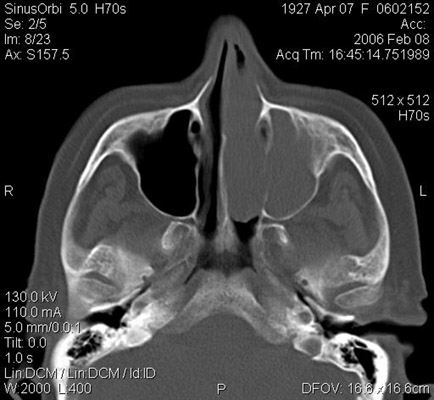

JFC Sinusitis maxilar. Espolón septal.